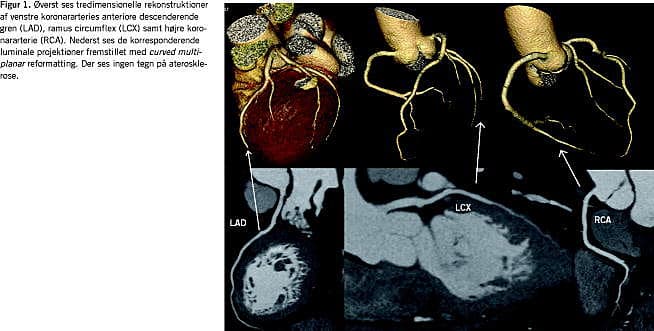

Billedanalysen foregår på en arbejdsstation med dedikeret software og vil typisk omfatte aksiale billedsnit i kombination med skrå og kurvede multiplanare rekonstruktioner gennem koronararterierne. Tredimensionelle rekonstruktioner er velegnede til at få overblik over koronaranatomien (Figur 1). Funktioner som automatisk vessel tracking, kantdetektion og kvantitativ stenosegradering er blevet almindelige i de fleste softwarepakker og har gjort evalueringen af koronararterierne hurtigere (Figur 2).

Ud over visualisering af det kontrastfyldte lumen giver CT-KAG også oplysninger om karvæggen og plaque -morfologien. Ikkestenoserende plaques og remodellering af karvæggen kan identificeres, ligesom eventuelle plaques kan karakteriseres som værende overvejende lipidholdige, fibrøse eller kacificerede (Figur 2). De kliniske implikationer af en sådan opdeling er dog fortsat uafklarede.